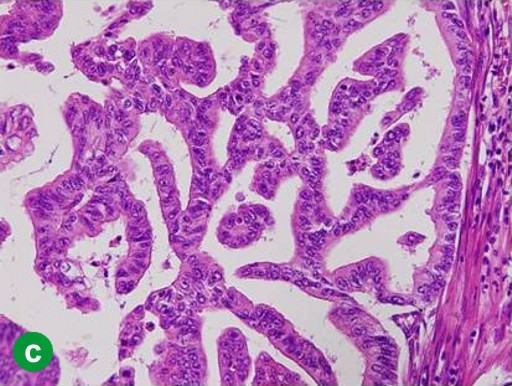

A 67-year-old man showed a pancreatic tumor on abdominal US at an annual medical checkup. An abdominal CT scan detected a 1 cm tumor in the body of the pancreas and main pancreatic duct dilatation of the distal pancreas (Figure 3a). A distal pancreatectomy with splenectomy was performed in February 2006. Histopathological examination confirmed a well-differentiated adenocarcinoma with no vessel or lymph duct invasion and no lymph node metastasis (Figure 3b). Mild atypical epithelia were observed at the cut edge of the main pancreatic duct (T1N0M0; R0; pathological stage: IA) (Figure 3c). Periodic checkups without adjuvant chemotherapy were carried out for 2 years, and there were no abnormal findings in abdominal CT scans or tumor marker assays.

|

Figure 3. Case#2: initial operation. a. A tumor approximately 1 cm in diameter and main pancreatic duct dilatation of the distal pancreas was detected in the pancreatic body on abdominal CT. b. Adenocarcinoma of the pancreas. Atypical cells with a swollen nucleus formed a papillary projection. c. Mild atypical epithelia projected from the cut edge of the main pancreatic duct. (H&E stain, x100). |